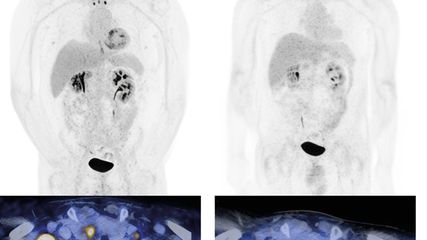

Par ailleurs, les résultats de l’étude OASIS-4 ont été présentés pour la première fois à l’ASCO.9 Ils ont montré que l’élinzanétant, nouvel inhibiteur dual de la neurokinine 1/3, réduisait significativement, par rapport au placebo, la fréquence des symptômes vasomoteurs modérés à sévères sous thérapie endocrinienne à 4 et 12 semaines (Fig.1). En outre, une amélioration numérique de la sévérité des symptômes a été observée à 4 et 12 semaines, ainsi qu’une augmentation significative de la qualité du sommeil et de la qualité de vie spécifique à la ménopause à 12 semaines.

Fig.1: Par rapport au placebo, l’élinzanétant a significativement réduit la fréquence des symptômes vasomoteurs modérés à sévères sous traitement endocrinien (modifiée selon Cardoso F et al.)9